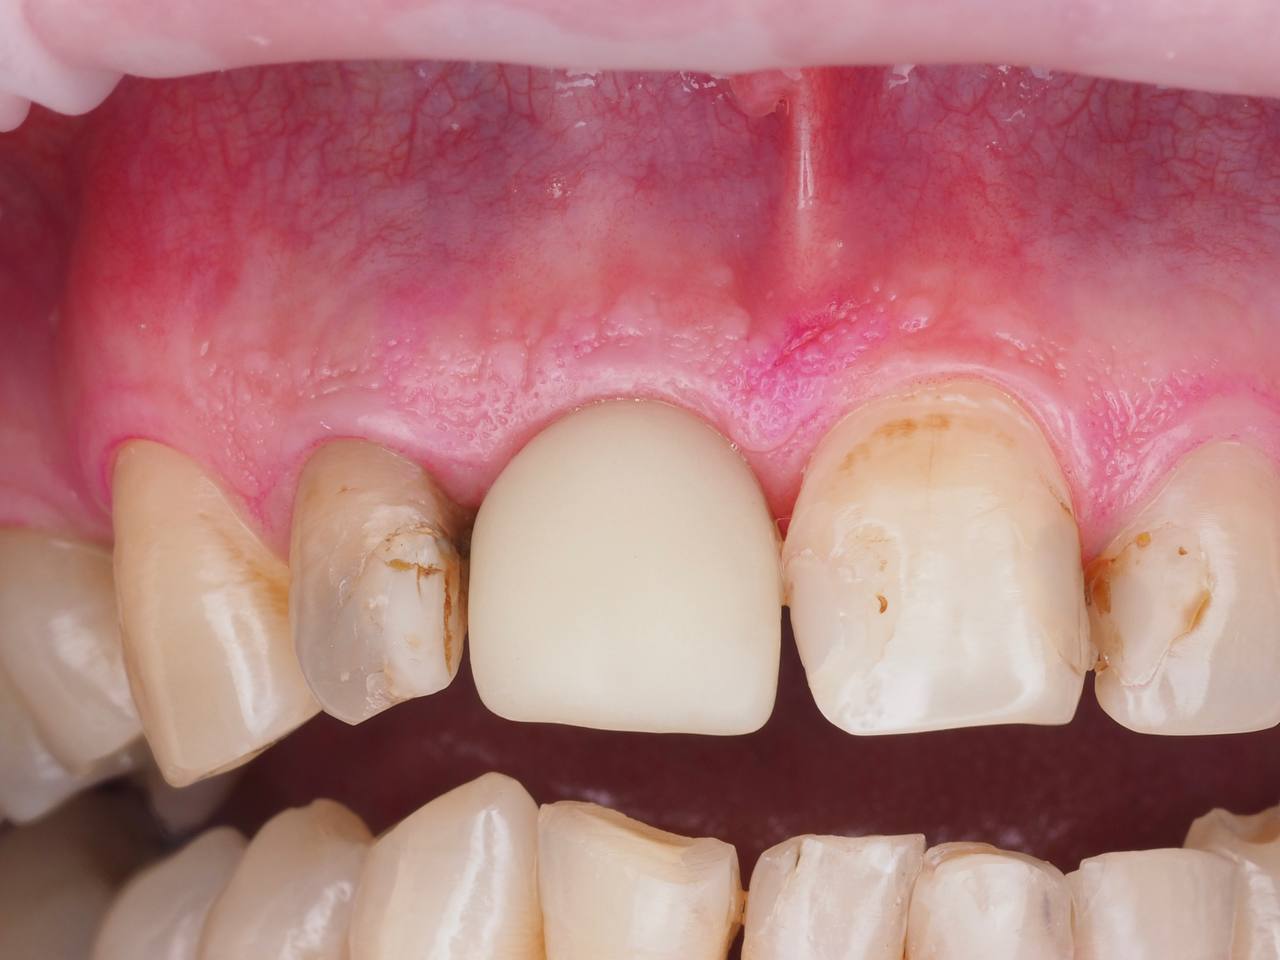

Одномоментная имплантация 1.1

AnyRidge, мультиюнит Octa, CCT, временная коронка